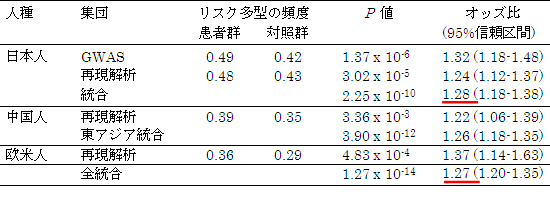

これらのSNPを、別のAIS患者786人と対照者24,466人からなる日本人集団について調べたところ、6番染色体上の1つのSNPでその相関が再現されました。2つの集団の結果を統合すると、最も強い相関を示すSNP(rs6570507)のP値[2](偶然にそのようなことが起こる確率)は2.25×10−10にもなり、日本人ではこのSNPを持つと発症のリスクが1.28倍高まることが分かりました(表1)。

さらにAIS患者743人と対照1,209人からなる中国人集団、およびAIS患者447人と対照737人からなる欧米人集団について調べたところ、どちらの集団でもこのSNPの相関が再現されました。したがって、このSNPが複数の人種においてAIS発症に関与することが分かりました。

表1 思春期特発性側彎症の段階的相関解析で発見された6番染色体上のSNP(rs6570507)の相関

- P値:相関の強さの指標。Cochran-Armitage trend testによる。P値(偶然にそのようなことが起こる確率)が低いほど、相関が高いと判定できる。

- オッズ比:相関の大きさ、リスク多型の影響力の指標。リスク多型を1つ持つごとにAIS発症リスクが1.27倍に高まる。

- 統合:GWASと再現解析の結果をMantel-Haenzel 法によるメタ解析で統合したもの。